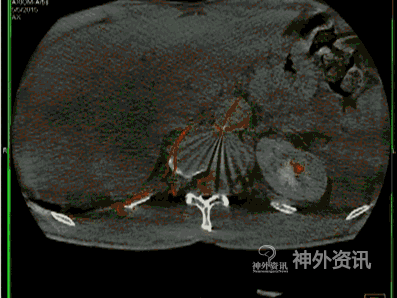

脊髓血管造影,尤其是经皮穿刺股动脉选择性脊髓血管造影,是诊断脊髓血管疾病的金标准。至今,由于影像技术、DSA血管造影机诸多后处理功能的进步,如三维成像技术(three-dimensional imaging technology;图1)、最大密度投影成像(maximum intensity projection,MIP;图2)、双容积重建(double volume,DV;图3)与三维影像融合技术(three dimensional image fusion technology;图4)及我们研究开发的三种技术的动态成像技术(dynamic image fusion technology),可以给出冠状位从前到后再从后到前、矢状位从左到右再从右到左、轴位从上到下再从下到上的全方位多角度动态立体解剖影像(图5),就更提高了对脊髓血管疾病诊断的认识和治疗水平。因此,应该说这些三维融合影像才是脊髓血管疾病诊断的金标准[1,2]。

图4: 右T12硬脊膜动静脉瘘(SDAVF),红色↑示瘘口,绿色↑示背侧引流静脉。A. 2D-DSA;B、C. 3D-DSA;D~F. 双容积重建冠状位、矢状位和轴位融合影像。

图4: G 动态双容积重建冠状位融合影像。

图4: H. 动态双容积重建矢状位融合影像。

图4: I. 动态双容积重建轴位融合影像。

图4: J~L. 最大密度投影(MIP)冠状位、矢状位和轴位融合影像。

图4: M. 动态旋转MIP。

图4: N~P. MRI/3D-DSA 三维融合冠状位、矢状位和轴位融合影像。